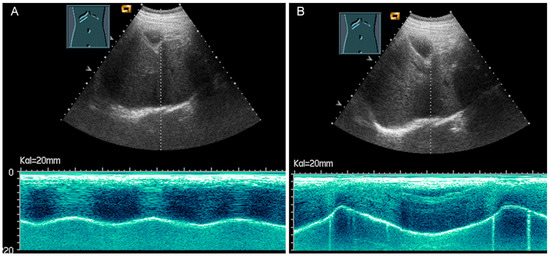

The thickness increase during inspiration was also used as a measure of muscle contraction. In most studies, an increase during inspiration of >20% is considered as normal [55] (Figure 31).

Figure 31.

Representation of diaphragm thickness in expiration (A) and inspiration (B) in pleural effusion (PE) and ascites (As).

Diaphragmatic excursion is measured in M-mode US with a low-frequency probe (2.5–5.0 MHz) in an anterior subcostal view through the liver window. The transducer should be positioned between the middle clavicular line and the anterior axillary line and directed medially, cranially, and dorsally to visualize the posterior third of the right diaphragm, approximately 5 cm lateral to the inferior vena cava foramen [52,53]. The amplitude (distance between the highest and the lowest points of the diaphragmatic movement) and the speed are measured in both quiet breathing and forced inspiration (the sniff maneuver) (Figure 32) [52,53]. The amplitude of diaphragmatic excursion is highly dependent on physical constitution and ranges from approximately 1–2 cm (resting breathing) to 7–9 cm (forced breathing) [59]. The diaphragm excursion can be determined only in spontaneously breathing patients.

Figure 32.

Illustration of diaphragmatic motility during quiet (A) and deep breathing (B) in a subcostal view.